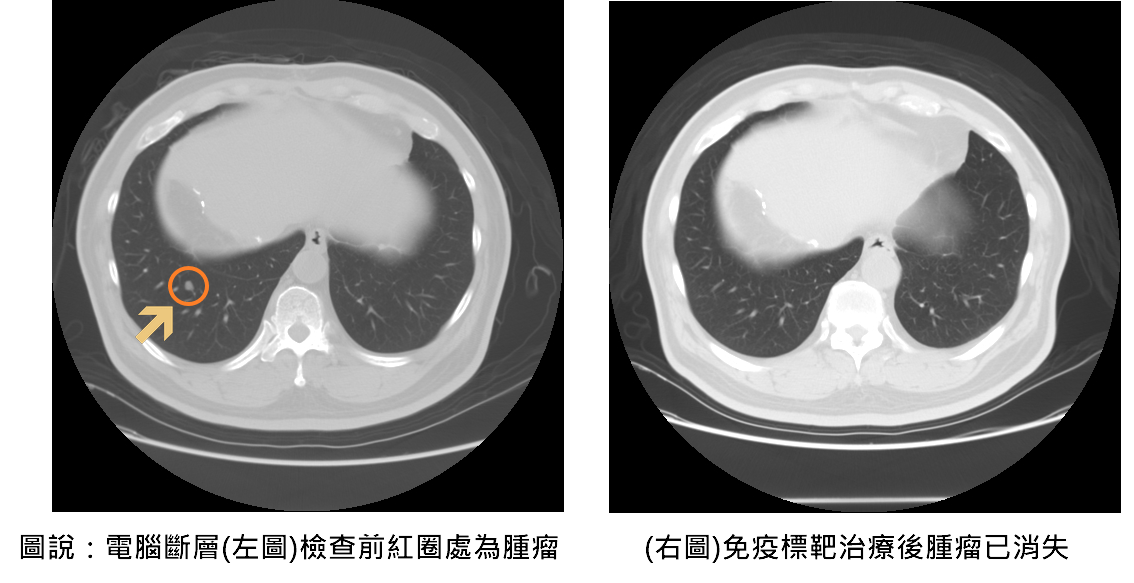

隨著2023年免疫標靶治療納入健保給付,大幅降低患者經濟負擔,也讓更多中晚期癌友得以接受有效治療。聯新國際醫院腸胃肝膽科醫師余青殷分享一位六十五歲患者,於兩年前接受肝癌切除手術,在術後例行追蹤時,發現甲型胎兒蛋白指數(AFP)持續飆高,以及肺部出現轉移的現象,經評估自體免疫狀況後,醫療團隊決定使用免疫標靶治療,採用第一線免疫標靶聯合療法—免疫藥物「癌自禦」與標靶藥物「癌思停」合併治療,三個月後AFP指數恢復正常,癌細胞亦完全消失,患者未出現任何不適或併發症,生活品質如常。